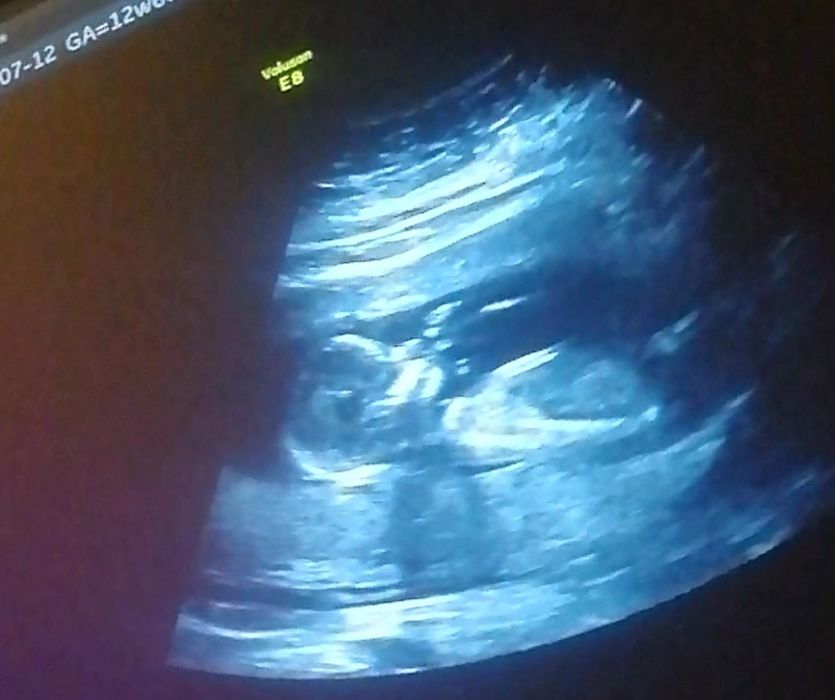

Liss, ну да, такой размер уже больше к 12 неделе подходит. Если бы это была беременность, там бы уже полноценный ребёночек с ручками и ножками был на этом сроке

Вот моя малыха на 12 неделе, так что это однозначно не плодное яйцо, а вот киста вполне возможна... У меня такая же была, только 10 см, пришлось оперировать, чтобы не лопнула